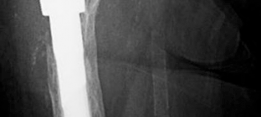

Fixation of the Augment

Screw Fixation:

Augments are typically fixed with multiple cancellous or cortical screws.

- Screws should achieve bicortical purchase where safely possible, avoiding neurovascular structures.

- Divergent screw trajectories enhance stability.

- Fluoroscopic guidance is often invaluable to ensure safe and adequate screw length and trajectory, particularly in the anterior-superior (near external iliac vessels) and posterior (near sciatic nerve) quadrants.

-

- This image likely shows an acetabular augment securely fixed with multiple screws into the host bone.

- This image could be a post-operative radiograph showcasing the completed reconstruction with an augment and revision cup. -

- Another post-operative X-ray providing a different view or illustrating a similar case. -

- A close-up radiographic view highlighting the augment and its screw fixation, along with the acetabular cup. -